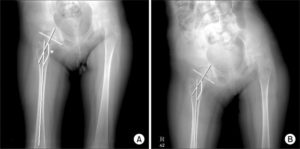

В процессе диагностики детской дистрофической coxa vara, а также приобретенной патологии у взрослых проводится рентгеновское исследование. В ходе процедуры в обязательном порядке осуществляется внутренний поворот ноги.

Первая фаза. В этом периоде еще отсутствует ясно выраженное скольжение эпифиза головки бедра. Иногда оно лишь намечается в виде поворота эпифиза, определяемого по рентгенограмме, сделанной в боковой проекции (положение Лауэшптейна).

На такой рентгенограмме можно видеть также нарушение структуры и декальцификацию хряща. Клинически определяется небольшая хромота, незначительный спазм мышц бедра и ограничение отведения.

Вторая фаза. Соскальзывание эпифиза ясно выражено. Оно происходит постепенно, причем головка ротируется, шейка, упираясь нижним концом в головку, смещается вместе с диафизом вверх. Между эпифизом и шейкой видна широкая светлая полоса.

В отдельных случаях такое смещение обнаруживается сразу, иногда— после небольшой травмы. В дальнейшем скольжение вверх шейки и диафиза бедра прогрессирует и достигает значительной величины.

Линия Шентона на рентгенограмме резко нарушена.